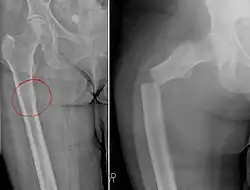

Chalkstick fracture due to bone metastasis of breast cancer. The left image shows the metastasis, on the right a pathological fracture a few days later.